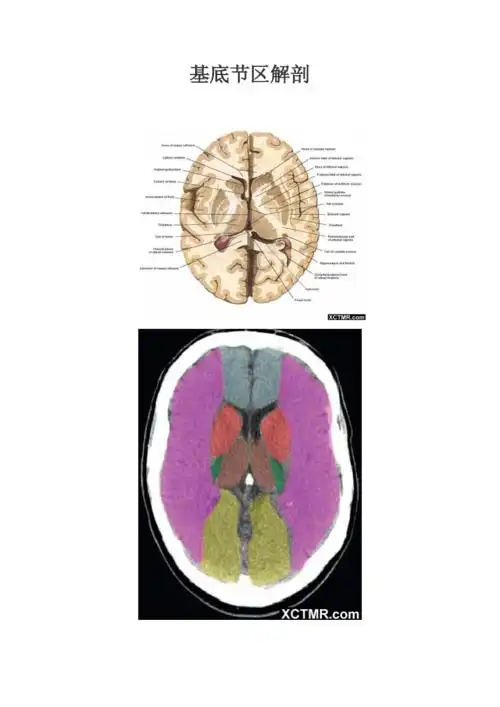

基底核与基底节区解剖与定位

【影像基础】值得收藏的基底节及周围区域解剖详图

基底节区层面颅脑ct断层解剖